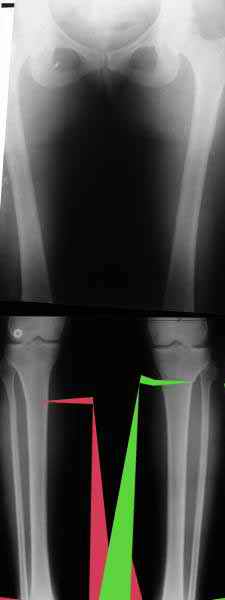

Вот, с учетом и без учета, и на разных уровнях...

AC> Вот, с учетом и без учета, и на разных уровнях...

AC> Саша Артемьев, может, для данного случая свой вариант нарисуешь?

Из приведнной схемы не совсеим понял что означают разноцветные линии.

И зачем латерализация периферического фрагмента. Я всегда делаю медиализацию. См схему. И для данного случая медиализация подходит как нельзя лучше.

a> Из приведнной схемы не совсеим понял что означают разноцветные линии.

Черные - это нынешняя механическая ось. Красные - это планируемая правильная ось.

a> И зачем латерализация периферического фрагмента.

;-) Читайте Палея. Стр. 114-115.

a> Я всегда делаю медиализацию. См схему. И для данного случая

Медиализация - это чисто эстетический прием, как я понимаю. Поскольку если делать остеотомию ниже вершины деформации, для восстановления оси надо делать смещение по ширине, в данном случае как раз латерализацию.

А вот на схемке без осей - там на разных уровнях (который правильнее?) устранение варуса чисто открытым клином без медиализации-латерализации. Если как-то так сделать - этого недостаточно будет?